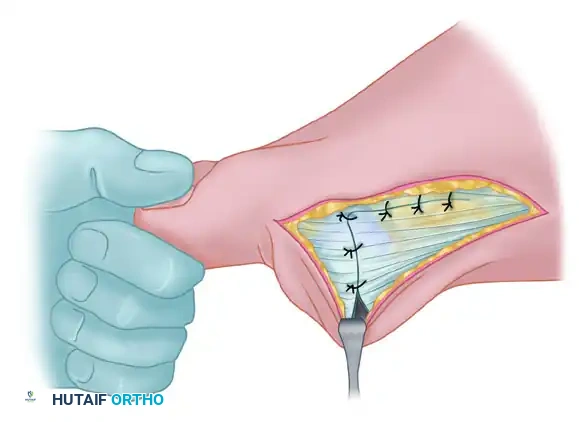

Medial Capsulorrhaphy and Closure

The final step is the medial capsulorrhaphy, which plicates the redundant medial capsule to hold the hallux in its newly corrected alignment.

- Hold the hallux in a congruently reduced position (approximately 0 to 5 degrees of valgus). Avoid over-correcting into varus.

- Excision of a redundant wedge of the medial capsule may be necessary.

- Imbricate the medial capsule, typically bringing the plantar flap over the dorsal flap, using strong, absorbable sutures (e.g., 2-0 Vicryl).

- Ensure the tension is sufficient to maintain the correction but not so tight as to restrict MTP joint plantarflexion and dorsiflexion.

- Deflate the tourniquet and achieve meticulous hemostasis.

- Close the skin incisions with non-absorbable monofilament sutures (e.g., 4-0 Nylon) using a horizontal mattress or simple interrupted technique.